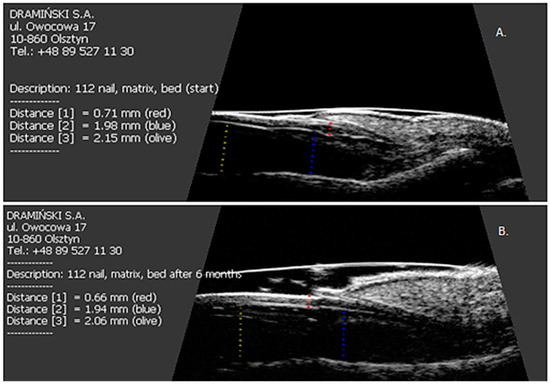

A total of 319 nails were examined: 190 nails in patients with psoriasis without arthritis and 129 nails in patients with PsA. Psoriatic changes in patients with Ps and PsA were present in 145 (76%) and 96 (74%) nails, respectively. Both the extensor tendon (Figure 1) and nail bed (Figure 2) in patients with PsA were thicker than in patients with psoriasis without arthritis (in both cases p < 0.001) and no statistical differences were observed in the thickness of nail plates and nail matrix. The nails with psoriatic changes were assessed in a US examination in regard to their morphology, in accordance with the classification proposed by Wortsman et al. (Figure S2). Focal hyperechoic involvement of the ventral plate (type I), loosening of the borders of the ventral plate (type II) and wavy plates (type III) in patients with psoriasis was observed in 83%, 11.5% and 5.5% of the nails under examination, respectively. No loss of definition of both plates (type IV) was observed. Type I, II, III and IV changes were present in 15.5%, 68%, 7% and 1.5% of the patients with PsA, respectively (Table 2). The digital extensor tendon was the thickest in type II of the changes in US in patients with Ps (p = 0.019), whereas no difference in the thickness of the extensor tendon was found in the group with arthritis depending on the type of changes of nail plates in an US examination. The thickness of the digital extensor tendon did not differ in patients with Ps and with PsA with the onycholysis and hyperkeratosis type changes (concomitant or existing separately), but it was significantly greater than in the pitting-type of changes (p = 0.041 and p = 0.033, respectively). A correlation was found in patients with Ps and PsA between the intensity of clinical changes in nails, as assessed with mNAPSI, with the thickness of the extensor tendon (r = 0.299, p = 0.042 vs. r = 0.336, p = 0.019, respectively). The tendon thickness in patients with Ps correlated with the matrix thickness (r = 0.346, p = 0.023) and the nail bed thickness (r = 0.285, p = 0.034), whereas in patients with PsA, the tendon thickness correlated with the nail bed thickness (r = 0.401, p = 0.011). No relationship between the thickness of the digital extensor tendon in a DIP joint with the intensity of skin changes was observed in either of the groups.

Figure 2. Initial US measurements of nail bed thickness in patients studied. p < 0.001. Ps: psoriasis, PsA: psoriatic arthritis.

All patients were started on methotrexate after the first US examination. After six months of treatment, a decrease in the thickness of nail plates, nail beds and nail matrix was observed in both study groups (Table 4 and Table 5, Figure 3). Methotrexate treatment in the group of patients without arthritis reduced the extensor tendon thickness (Table 4, Figure 1), whereas no such effect was observed in patients with PsA (Table 5, Figure 1 and Figure 4). Methotrexate treatment in both groups reduced the intensity of vascularization as assessed with PD at entheses under study. An intensified PD signal in Ps patients after treatment was observed in 42/190 (22%) nails, like in the PsA group, where it was 29/129 (22.5%) nails.

Figure 3. The effect of six months of methotrexate treatment on the thickness of the nail plate, nail bed and nail matrix in patients studied. (A) Before treatment; (B) after six months of therapy.